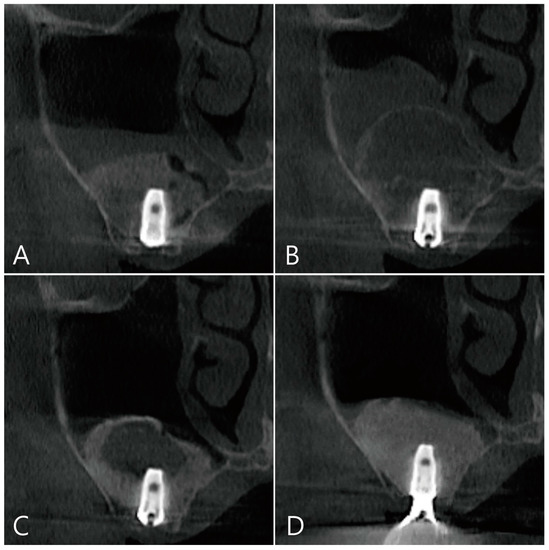

CBCT was taken immediately after MSA, one week after surgery, and before the uncovering procedure (Figure 3A–C). On the coronal image of the CBCT taken immediately after surgery, it was confirmed that MSA and implant placement were performed at the same time, and no dislocation of the bone graft particles was observed (Figure 3A). On the coronal image of the CBCT taken one week after surgery, severe grafting voids occurred on the upper part of the implant apex, and the maxillary sinus membrane was also thickened severely (Figure 3B). On the CBCT taken just before the uncovering procedure, the grafting void decreased in size, but a radiolucent image resembling SCC was observed. The thickened maxillary sinus mucosa was also reduced (Figure 3C). The grafting void was removed and a prosthesis was delivered. On the CBCT taken 6 months after the prosthesis was delivery, the radiopacity of the removed grafting void site was increased (Figure 3D).

Figure 3. (A) Coronal image of the CBCT taken immediately after surgery. There was no perforation of the maxillary sinus membrane and no leakage of the bone graft substitute; (B) coronal image of the CBCT taken one week after surgery. A severely enlarged grafting void was observed above the implant apex, and the ostium was obstructed due to severe membrane thickening; (C) coronal image of the CBCT taken 6 months after surgery. Although the grafting void was reduced in size, it appears similar to the SCC; (D) the radiopacity of the removed grafting void site was increased in the CBCT images taken 6 months after the prosthesis was delivered.